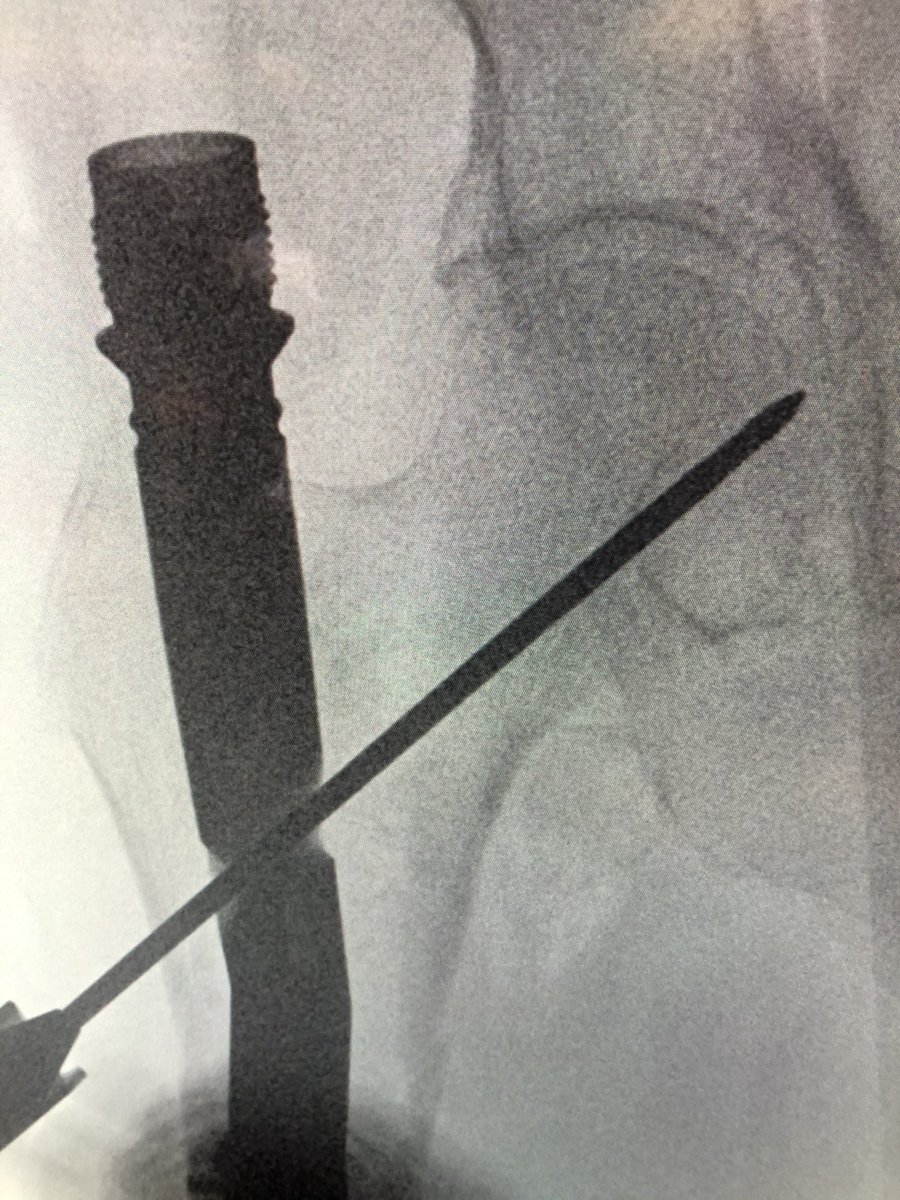

[1/2] Always make sure your wire stays where you put it. The original wire placement for drilling was this, but after drill came out so did the wire, and the screw was placed over the wire without ascertaining that it was back in proper position...

[2/2] This resulted in a completely different (anterior) trajectory of screw placement (left), which then had to be corrected (right). So always check.